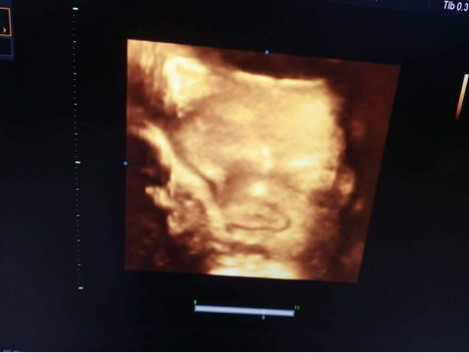

อายุครรภ์35w1น้ำหนัก2700

ท้องแข็งนานมากแต่ละครั้ง วันนี้เลยไปหาหมอแต่ปากมดลูกยังไม่เปิดหมอบอกช่วงนี้เริ่มแข็งปั่นแล้วน้องก็กลับหัวแล้ว หมอบอกถ้าแข็งทุก10นาทีให้ไป รพเลย ได้เห็นน้องด้วยวันนี้